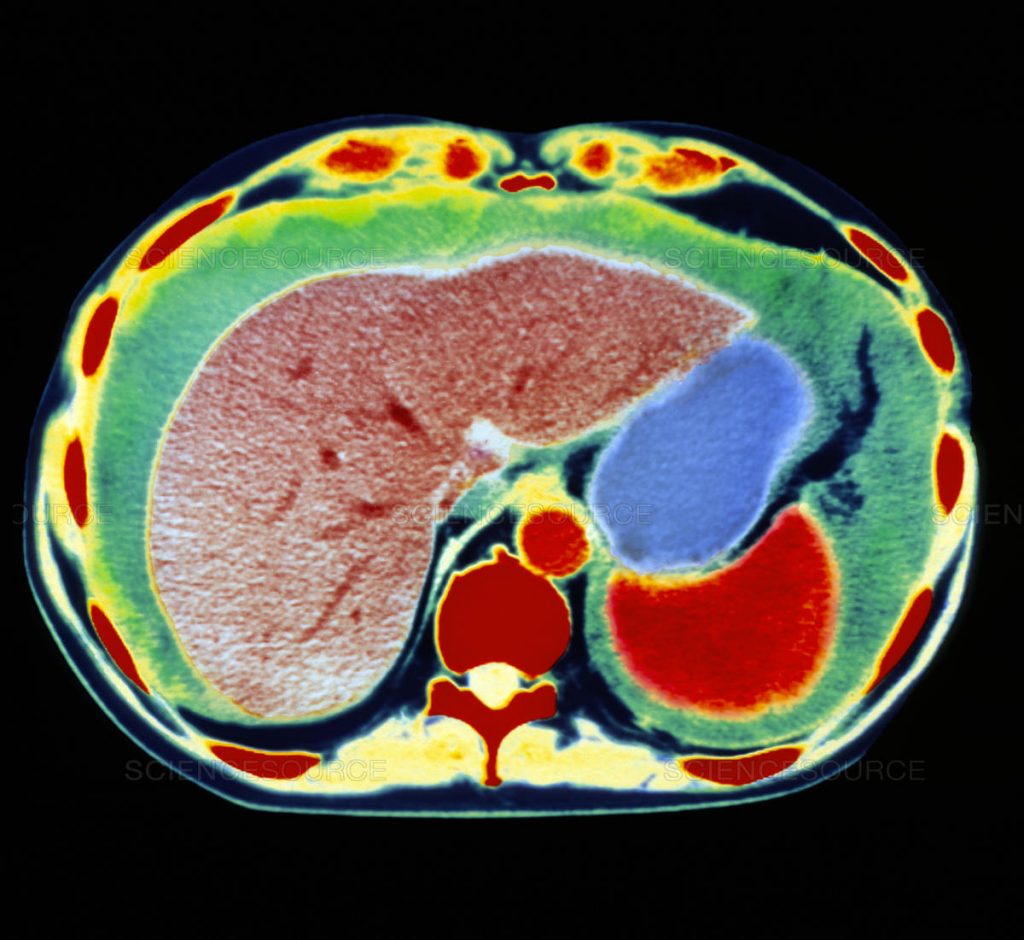

Η διάγνωση γίνεται με υπερηχογράφημα, αξονική και μαγνητική τομογραφία.

Γίνεται διαγνωστική παρακέντηση, λαπαροσκόπηση, υπέρηχος, μαγνητική τομογραφία, αξονική τομογραφία